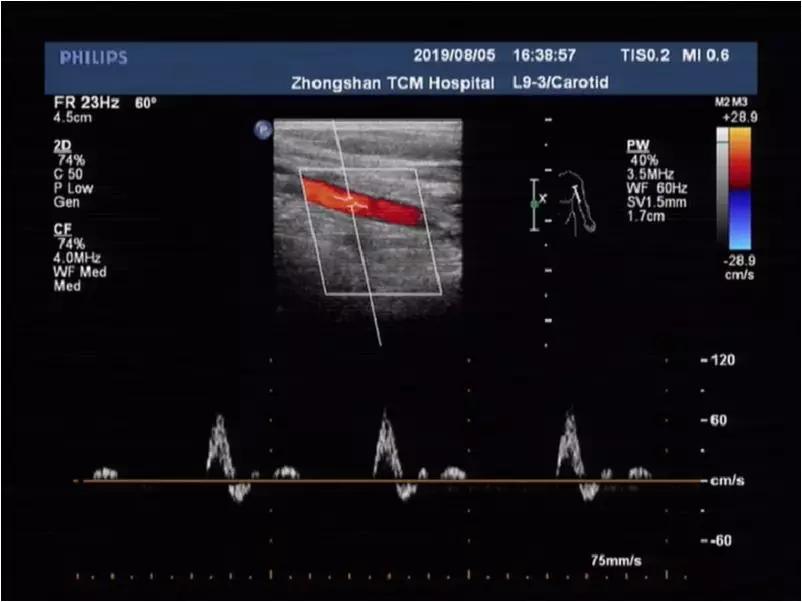

自然体位:上肢动脉流速正常,高阻力